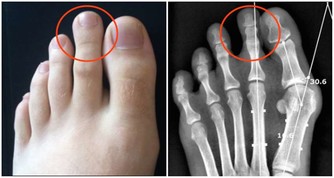

▼4. 匙狀指甲

若指甲看起來是匙狀,則可能代表患上了小細胞低色素貧血症,即紅血球比正常還要淡色。此外,也有可能是患上了血色沉著病,一種因為鐵過剩的肝臟病症。同時,匙狀的指甲也可以說心臟病或甲狀腺功能減退而出現的症狀。